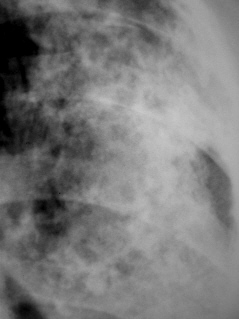

Иллюстрации 1, 2. Тотальное снижение прозрачности легочной ткани слева значительной интенсивности, неоднородной структуры. Средостение несколько смещено влево. Справа определяется компенсаторная эмфизема, слева умеренно выраженный плеврогенный цирроз.

Иллюстрации 3, 4. Фрагменты рентгенограмм с увеличением. Структура затемнения неоднородная, ноздреватая. На боне интенсивного затемнения визуализируются округлые участки просветления. Местами определяются более интенсивные участки затемнения известковой плотности в виде «очаговости».